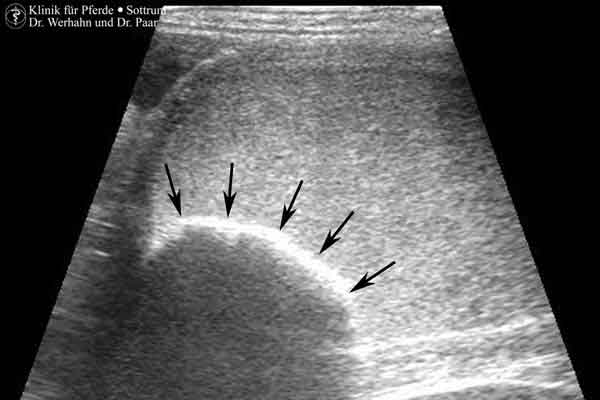

Flüssigkeitsansammlungen in der Gebärmutter, Verdickungen und Veränderungen der inneren Auskleidung der Gebärmutter sind Anzeichen für eine gestörte Selbstreinigung und / oder Gebärmutterentzündung. Im Rahmen chronischer Umbauvorgänge (Endometritis/Endometrose-Komplex) in der Gebärmutterschleimhaut können auch sogenannte Endometriumzysten auftreten. Erreichen diese Endometriumzysten eine gewisse Größe können sie negative Auswirkungen auf die Trächtigkeitsrate haben. Außerdem erschwert das Vorkommen von Endometriumzysten die Diagnostik der frühen Trächtigkeit, da eine Verwechslungsmöglichkeit mit einer Fruchtanlage besteht. Mehr zu der transendoskopische Behandlung von Endometriumzysten finden Sie auf unserer Seite zur Hochfrequenzchirurgie (Radiofrequency-Surgery).